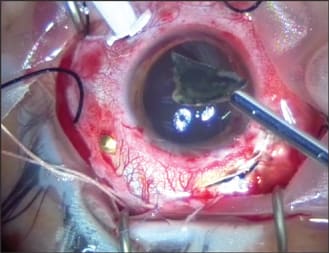

A 20-year-old male sustained an intraocular foreign body (IOFB) in his left eye by hitting a hammer against a large metallic object. He presented to the emergency room 1 day after the injury. On examination, his visual acuity was 20/200, and a large nasal conjunctival hemorrhage was observed with hypotony and clear cornea and lens. On indirect funduscopy, a metallic intraocular foreign body was observed stuck in the inferior retina at the equator with a local retinal detachment, whitening of the retina around its edges, and a mild vitreous hemorrhage. The intraocular foreign body was demonstrated on orbital CT (Figure 1). An exploration revealed a 4 mm entry wound, extending posteriorly from the limbus at the nasal side. The wound was sutured with Vicryl 7/0 suture, an encircling #41 solid silicone band was placed (Figure 2), and a pars plana vitrectomy was performed during the primary procedure. The intraocular foreign body was released from its adhesions to the retina (Figure 3) and removed with a magnet (Figure 4) through a previously prepared sclerotomy, revealing a large retinal tear (Figure 5). The intraocular foreign body outside the eye is shown in Figure 6.

Figure 2. View of sutured entry wound and band.